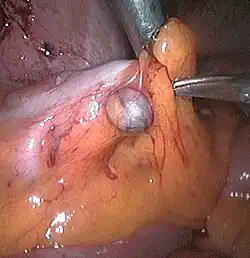

Die Divertikulose ist eine Veränderung des Dickdarms in Form von kleinen Ausstülpungen der Darmwand. Bei diesen Ausstülpungen wird von falschen Divertikeln gesprochen. Falsch werden sie genannt, da hier im Gegensatz zu den echten Divertikeln nur die Schleimhaut und nicht die ganze Darmwand ausgestülpt wird.